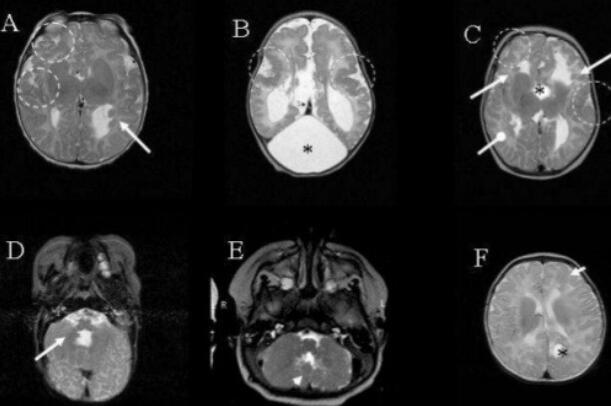

Magnetic resonance imaging (MRI) of the brain is a key diagnostic tool of AGS.

An MRI can detect patterns in the brain tissue that are characteristics of AGS. When analyzing the MRI, the doctor will look for areas of calcium buildup and shrinking of unusually small areas of the brain.